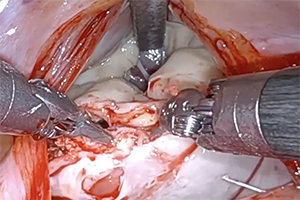

Vol 11, No 6 (November 29, 2022): Robotic Mitral Valve Surgery II

Vol 11, No 5 (September 30, 2022): Robotic Mitral Valve Surgery I